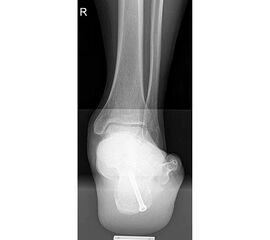

715.<br> Für die medialisierende Calcaneusosteotomie wird ein bogenförmiger Hautschnitt in Höhe des hinteren Fersenbeines gesetzt, die Subcutis bis zum Fersenbein durchtrennt und dieser bogenförmige Lappen nach ventral präpariert. Dadurch kommt es zu einem Schutz des Nervus suralis, welcher gemeinsam mit den Peronealsehnen nach vorne gehalten wird.<br> Es wird nun das Fersenbein mit einem Wundspreizer eingestellt und cranial sowie caudal mit 2 Hohmannhaken umfahren.<br> Dann wird das Fersenbein mit der oszillierenden Säge osteotomiert, mit dem Meißel und dem Wundspreizer distrahiert.<br> Danach wird das Fersenbein ca. 1 cm nach medial verschoben, unter Vermeidung der Cranialisierung des hinteren Calcaneus . Dann wird von dorsal über eine Hautstichincision der Bohrdraht für die 4,5mm (- 6,5 mm) kanülierte Schraube eingebracht und über die Osteotomie in den vorderen Calcaneusanteil vorgeschoben.<br> Kontrolle im Bildwandler in 2 Ebenen. Wenn die Bohrdrahtlage gut ist Überbohren für die kanülierten Schrauben und Eindrehen der Schraube. (Alternativ kann an Stelle der Schraubentechnik auch eine Fixation mit Stufenplatten oder Ähnlichem verwendet werden).<br> Wundverschluss am lateralen Zugang und über der Stichincision.</p>"> 715.<br> Für die medialisierende Calcaneusosteotomie wird ein bogenförmiger Hautschnitt in Höhe des hinteren Fersenbeines gesetzt, die Subcutis bis zum Fersenbein durchtrennt und dieser bogenförmige Lappen nach ventral präpariert. Dadurch kommt es zu einem Schutz des Nervus suralis, welcher gemeinsam mit den Peronealsehnen nach vorne gehalten wird.<br> Es wird nun das Fersenbein mit einem Wundspreizer eingestellt und cranial sowie caudal mit 2 Hohmannhaken umfahren.<br> Dann wird das Fersenbein mit der oszillierenden Säge osteotomiert, mit dem Meißel und dem Wundspreizer distrahiert.<br> Danach wird das Fersenbein ca. 1 cm nach medial verschoben, unter Vermeidung der Cranialisierung des hinteren Calcaneus . Dann wird von dorsal über eine Hautstichincision der Bohrdraht für die 4,5mm (- 6,5 mm) kanülierte Schraube eingebracht und über die Osteotomie in den vorderen Calcaneusanteil vorgeschoben.<br> Kontrolle im Bildwandler in 2 Ebenen. Wenn die Bohrdrahtlage gut ist Überbohren für die kanülierten Schrauben und Eindrehen der Schraube. (Alternativ kann an Stelle der Schraubentechnik auch eine Fixation mit Stufenplatten oder Ähnlichem verwendet werden).<br> Wundverschluss am lateralen Zugang und über der Stichincision.</p>" srcset="/assets/images/a/3-raswd6qgkh6s353.jpg 1x, /assets/images/g/3-exngvjjv83x827d.jpg 1.5x, /assets/images/w/3-836r57qt8j3eh0w.jpg 2x" width="270" height="240" loading="lazy">

Abbildung 4